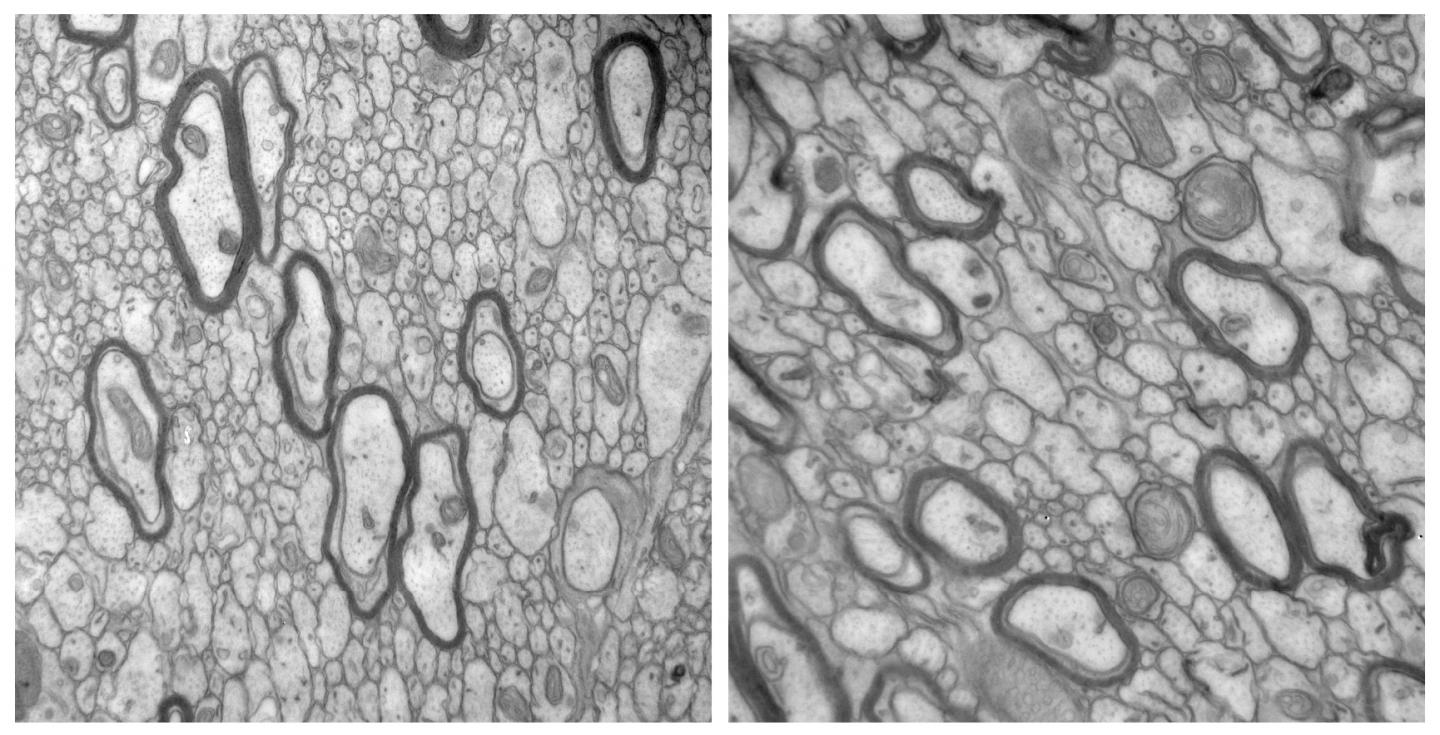

TSC is caused by mutations in the genes TSC1 and TSC2. The disease affects approximately 1 in 6,000 people and is characterized by the growth of numerous benign tumors in different tissues of the body, including the brain, skin, eyes, kidneys, heart, and lungs. Many patients also have neurological symptoms such as epilepsy, intellectual disability, and autism. Patients' brains show various abnormal structures. In particular, TSC patients with autism show defects in the organization of their white matter, the regions of the brain where oligodendrocyte cells protect neuronal axons by wrapping them in an insulating myelin sheath.

Mustafa Sahin and colleagues previously found that mice whose neurons lack TSC1 fail to myelinate their axons correctly, but the reason for this defect remained unclear. Sahin's team at Boston Children's Hospital and Harvard Medical School now reveal that neurons lacking TSC1 secrete increased amounts of a protein called connective tissue growth factor (CTGF) and that this protein impedes oligodendrocyte development and myelination. Deleting the gene encoding CTGF restored the ability of oligodendrocytes to myelinate axons in mice lacking neuronal TSC1.